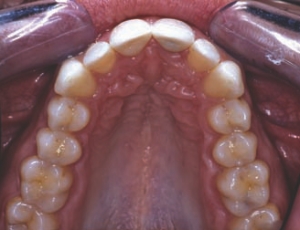

FIGURE 31--Maxillary occlusal 1:2 post-op.

Maxillary anterior crowns provide an exciting challenge to our artistic and technical abilities and call upon our knowledgeof smile design principles of proportion, symmetry, harmony and tooth morphology. Smile rejuvenation can positively impact a patient’s selfesteem and emotional health through improved appearance. 9 Excellent soft tissue health and correct tooth contours and emergence profiles are … Read more